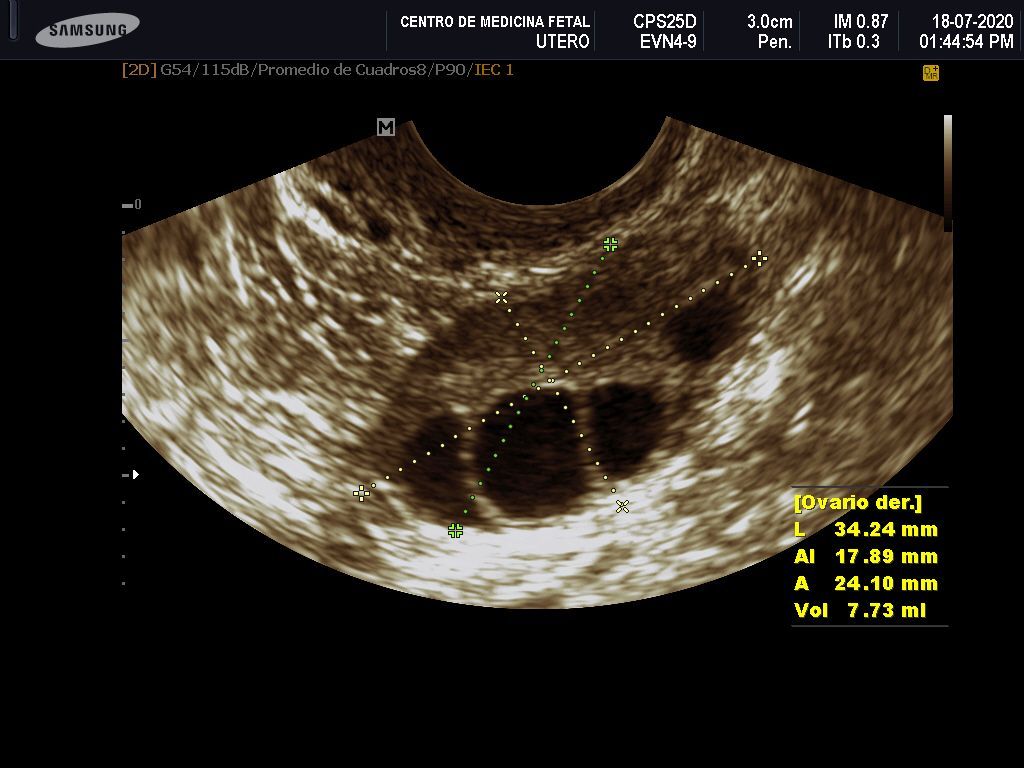

- Detección ecográfica transvaginal o pélvica y tratamiento de: Miomas, quistes de ovario, endometriosis, malformaciones uterinas